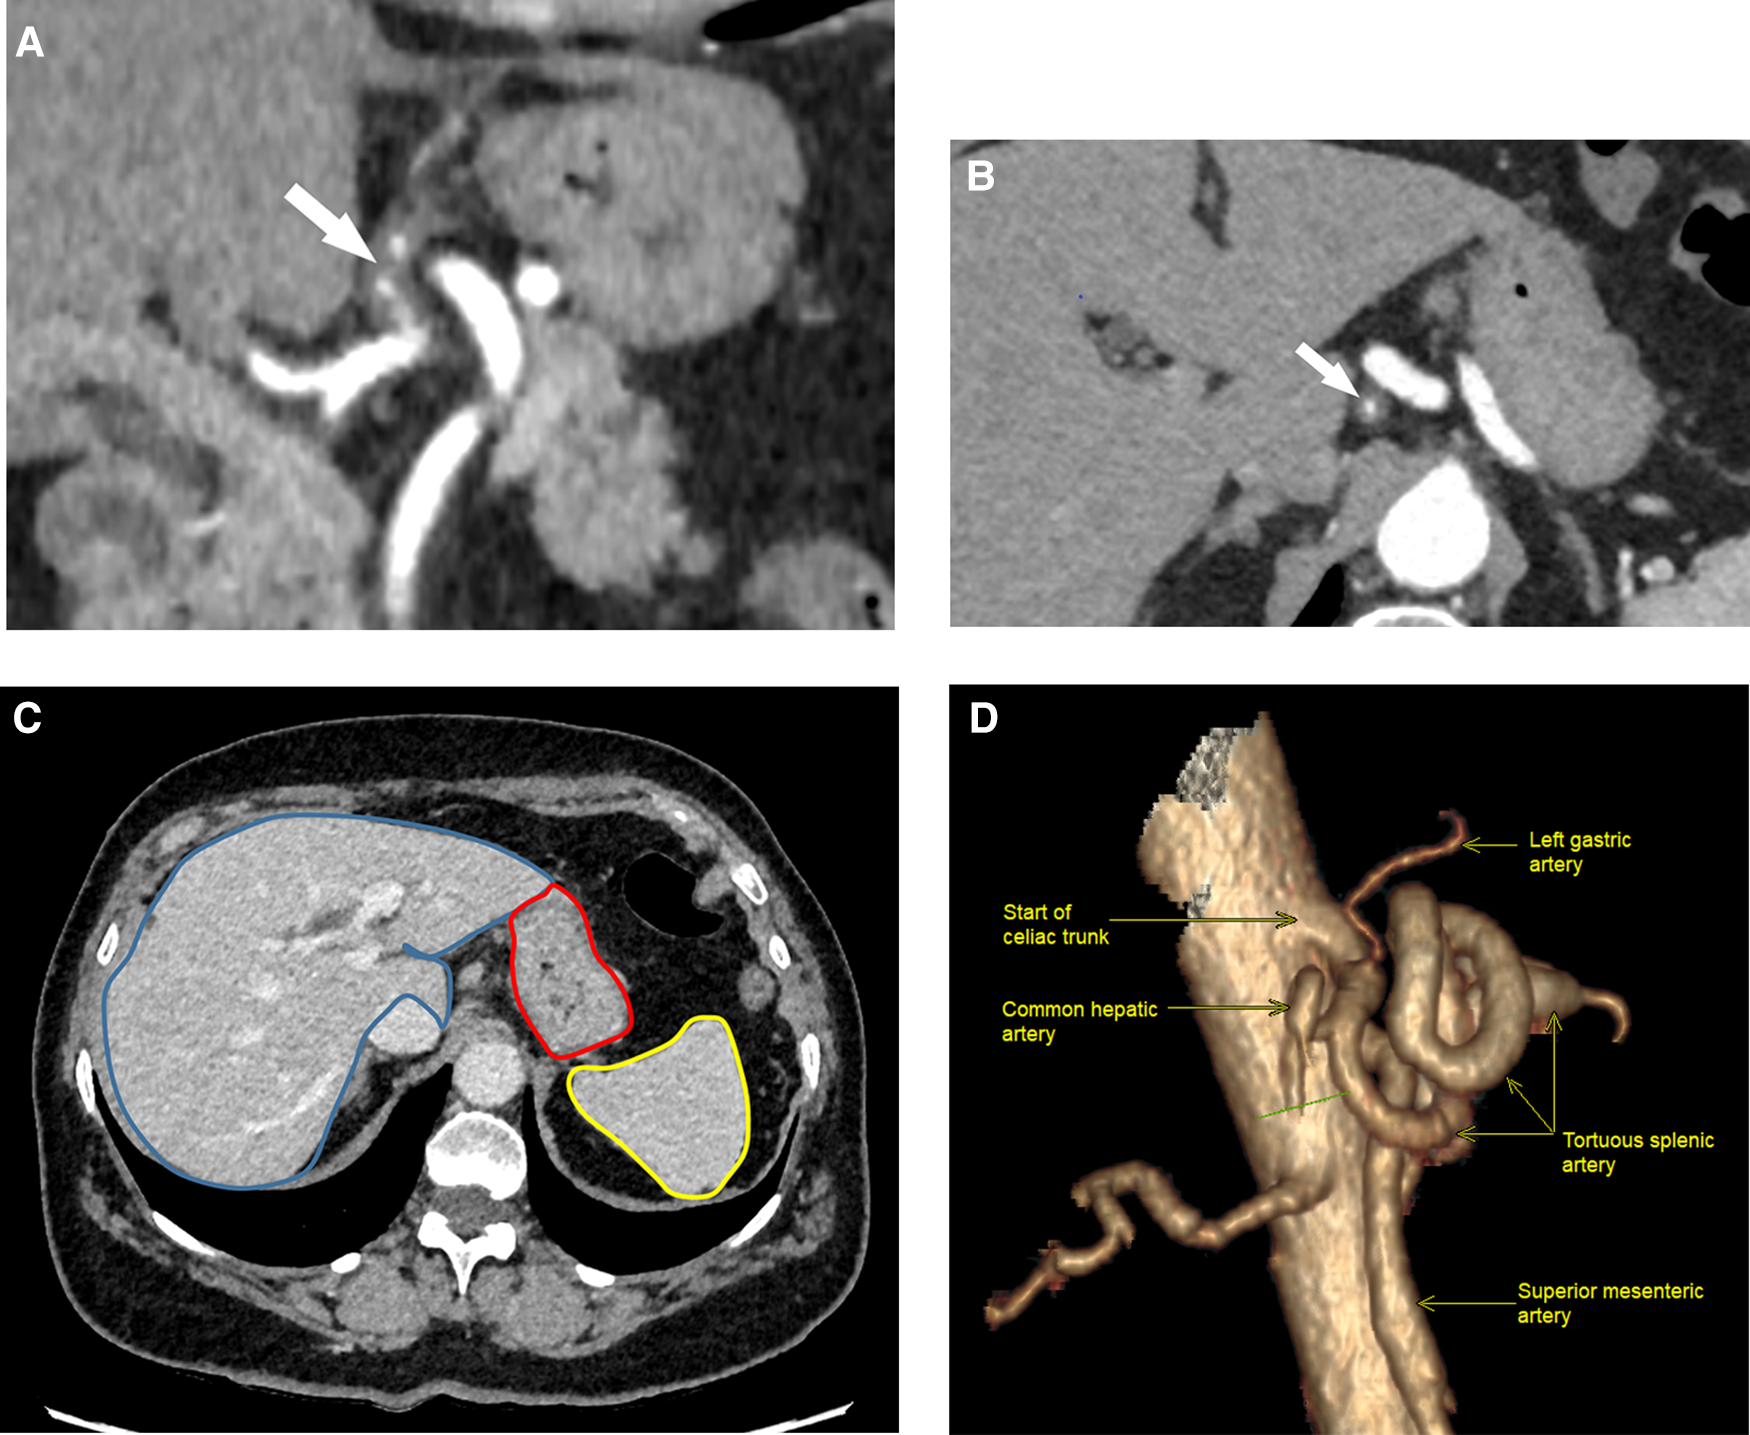

A 69-year-old Caucasian female was admitted to the emergency department due to acute epigastric pain that had spontaneously occurred during a yoga session while doing a “bridge stretch” (reclined backbend) and had persisted for the past 24 h. On admission, she reported experiencing epigastric pain and nausea but had not vomited. Her medical history was notable for arterial hypertension and a laparoscopic cholecystectomy that had occurred one year prior. Physical examination revealed upper abdominal tenderness and abdominal guarding upon deep palpation. While vital parameters were within the normal range, blood pressure was elevated at 186/114 mmHg with a normal heart rate of 72 bpm. Laboratory tests indicated slightly elevated CRP levels at 7.4 mg/L (normal range <5) with normal total leucocyte count. Blood pressure was treated with a short-acting calcium antagonist per os. An abdominal ultrasound scan showed no abnormalities, but due to persistent abdominal pain, a computed tomography angiography (CTA) was ordered to rule out mesenteric ischemia. Imaging revealed patency of the celiac trunk and both mesenteric arteries, along with an aberrant left hepatic artery (LHA) originating from the distal part of the LGA. The arterial wall of the LGA from its origin up to the aberrant LHA was thickened, with partial thrombosis of the lumen, indicating isolated arterial dissection. No associated aneurysm or signs of organ malperfusion were observed (Figures 1A–D).

Figure 1

Helicoidal 512 slice computed tomography angiography in arterial phase with 1.3 mm slices. (A) Sagittal view showing eccentric wall thickening of the LGA (arrow) from its start of the coeliac artery, evoking a dissection. (B) Coronal view of LGA dissection showing a diffuse irregular luminal narrowing (arrow). LGA, left gastric artery. (C) Normal perfusion of gastric wall (red mark), liver (blue mark) and spleen (yellow mark) in portal phase. (D) 3D-reconstruction of the celiac trunk anatomy (right lateral view, 90°).